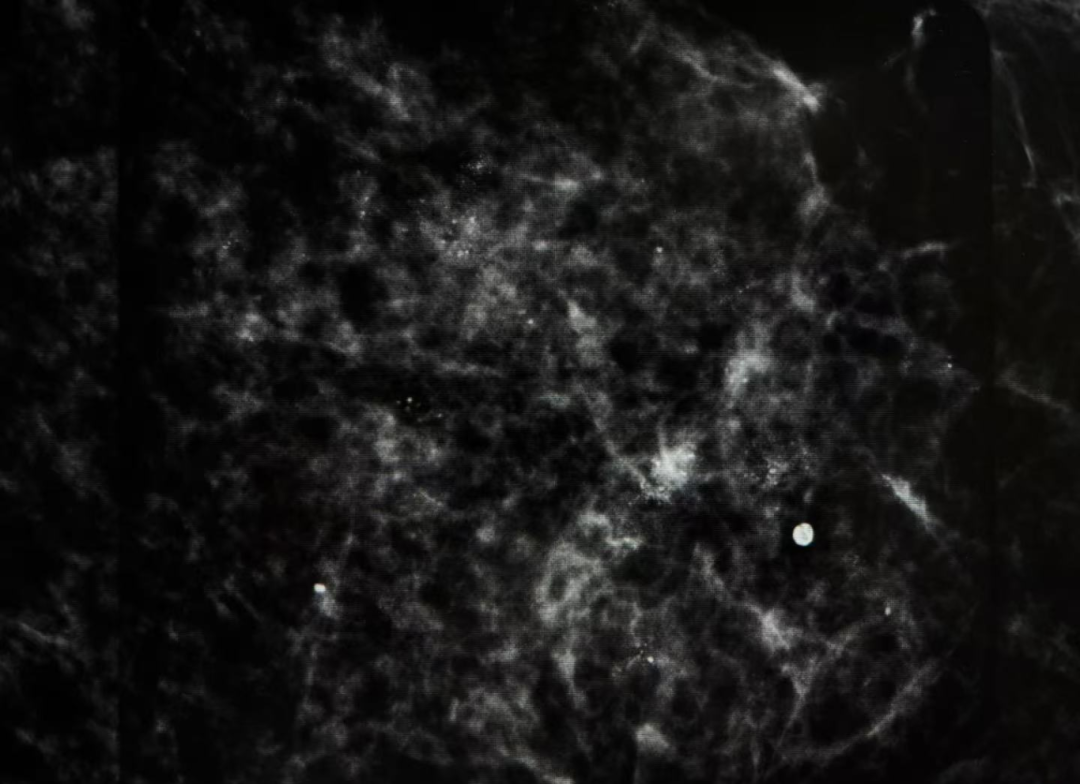

▲彩超发现不了的微小钙化